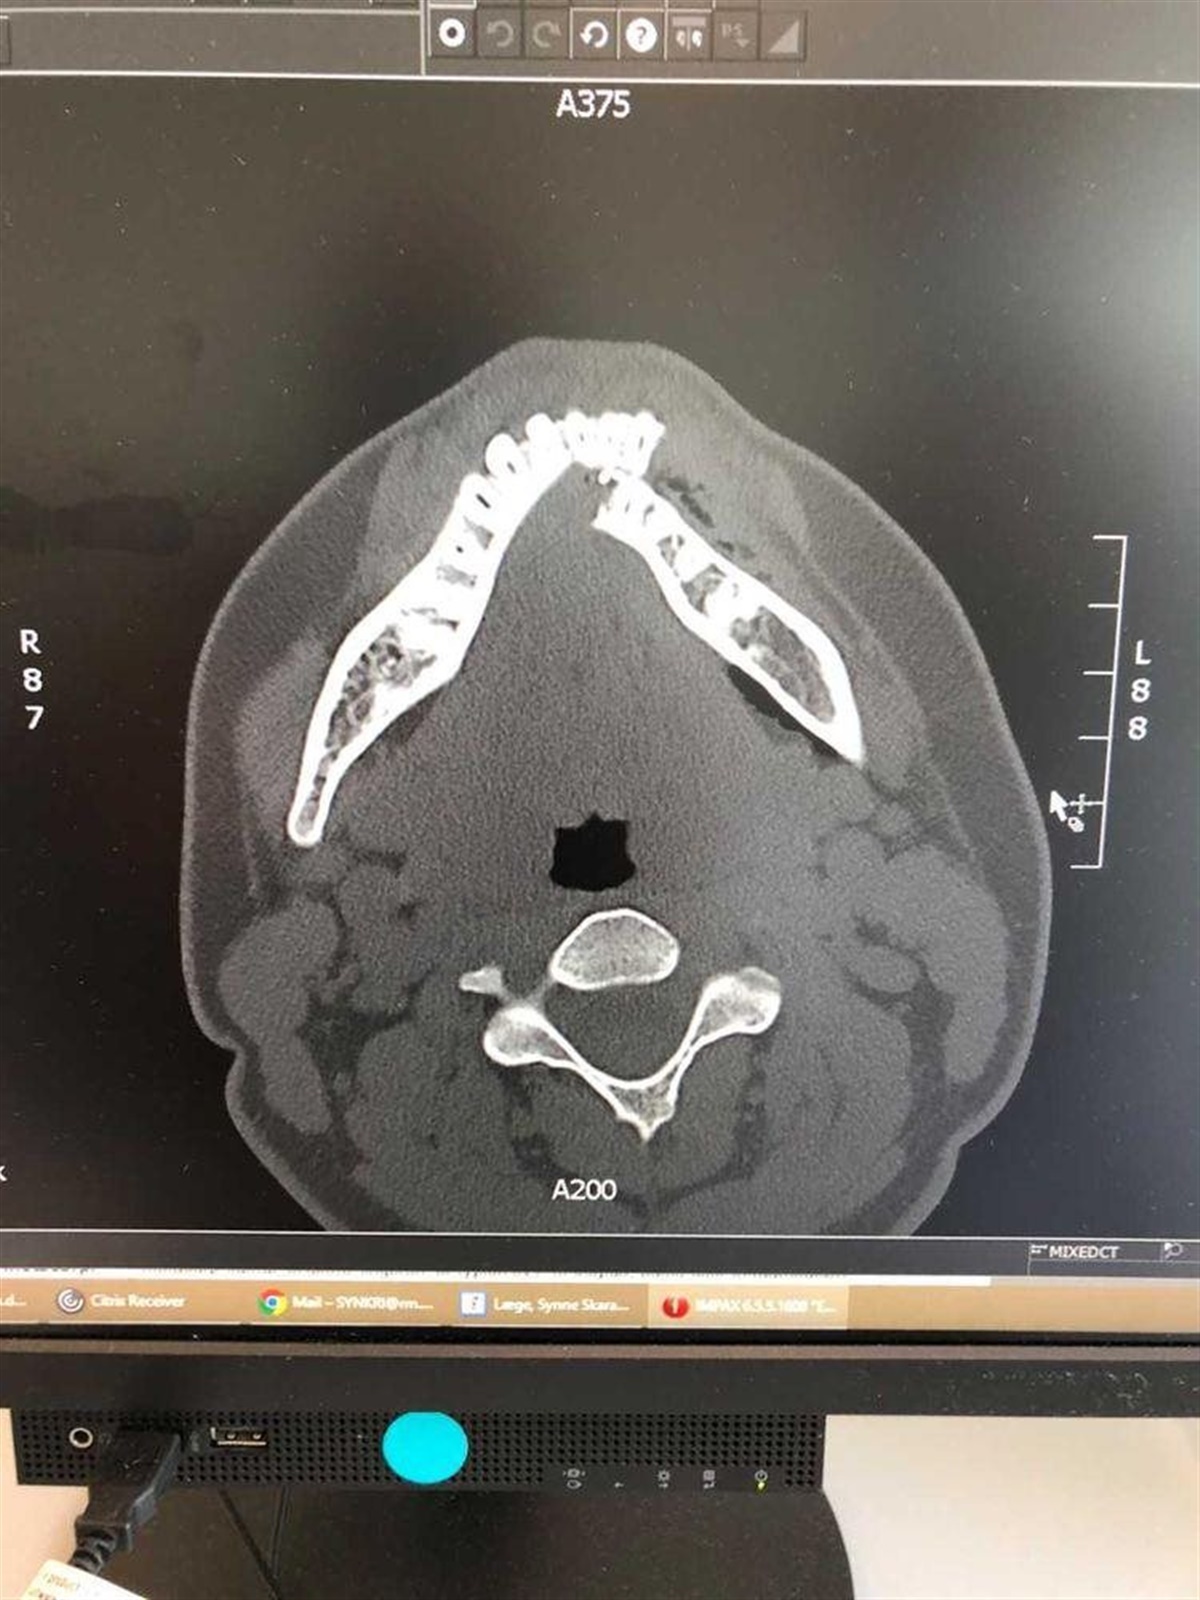

Amalie blev sat på en stol, mens hendes mor ringede efter en ambulance. Kort efter kom der både en ambulance og en lægebil, og det blev meget hurtigt konstateret at Amalie havde brækket kæben.

Amalie Nanfeldts brækkede kæbe. Foto: Privat

– Alle mine tænder i venstre side af undermunden, var skubbet helt ind til tungen, fortæller Amalie.